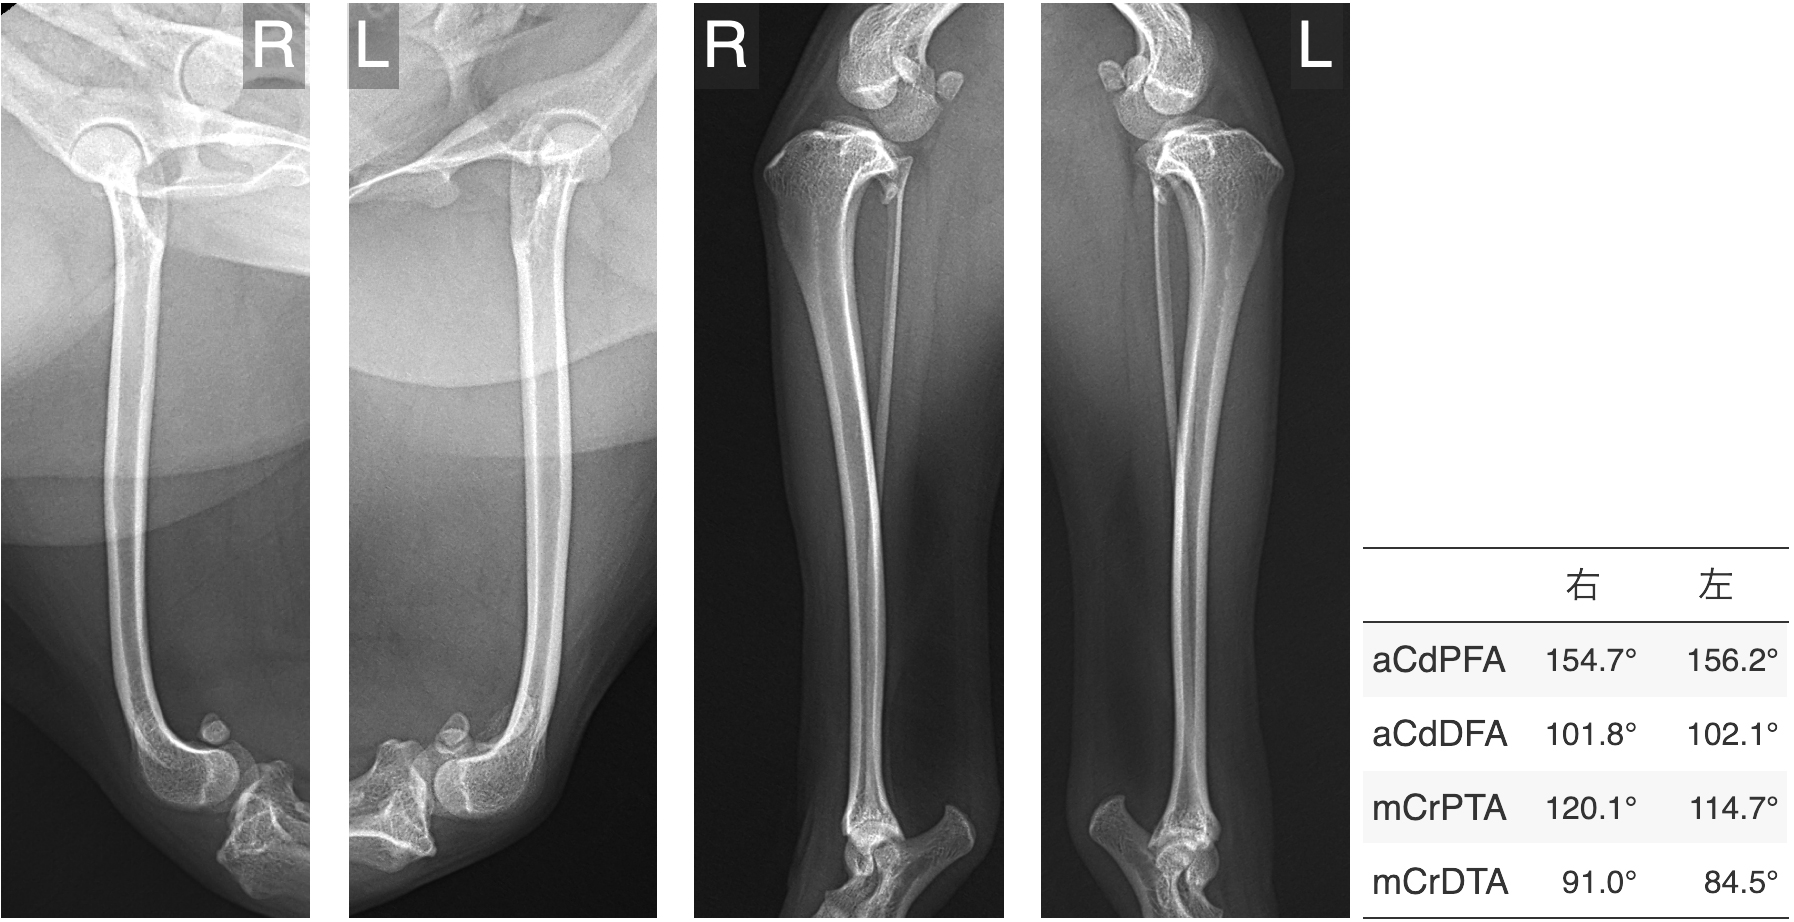

レントゲン検査で骨の変形が疑われる場合には、より詳しい評価のためにCT検査をおすすめしています。

レントゲンでは全体像はつかめても、骨の捩れや傾きといった詳細な情報までは正確に把握できないことがあるからです。

以下は、グレード4の膝蓋骨脱臼でよくみられる骨の変形の一例です。

ただし、骨の変形は症例ごとにその部位や程度が異なるため、CTによる三次元的な形態解析を行うことが、適切な手術計画を立てるうえで重要です。